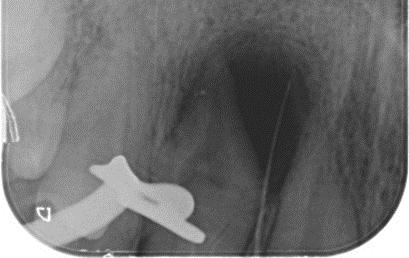

Dens Invaginatus (DI), a relatively uncommon developmental dental anomaly characterized by the invagination of enamel and dentin into the tooth structure, particularly the Type III variant which extends beyond the cementoenamel junction and possesses its own independent apical foramen, presents intricate endodontic challenges stemming from its often highly complex and unpredictable internal anatomy. Successful management requires a meticulous and tailored approach. This case report details the successful non-surgical root canal treatment of a Type III DI in a 15-year-old male's maxillary lateral incisor (tooth 12) with a pulpless, infected root canal system and a chronic apical abscess attributed to the DI defect. Preoperative evaluation involved clinical examination and periapical radiographs. While cone-beam computed tomography (CBCT) offers detailed visualization of such anomalies, its use was avoided to minimize radiation in this young patient. Clinical findings and conventional radiographs were deemed sufficient for treatment planning.

The endodontic therapy was conducted over four appointments. Access cavities were precisely prepared for both the main canal and the invagination, guided by a dental operating microscope. Working lengths were determined electronically and confirmed radiographically. The main canal was shaped using rotary files. The narrow, irregular invagination was meticulously instrumented with hand files, utilizing both EDTAC and copious sodium hypochlorite irrigation for thorough cleaning and disinfection. Calcium hydroxide mixed with Ledermix was used as the initial intracanal medicament to address infection and inflammation.

The fourth appointment involved re-access, final EDTA irrigation, and obturation. The main canal was obturated with a single gutta-percha cone and AH-26 Cement. Due to the invagination's complex morphology, a thermoplasticized injectable gutta-percha system ensured complete three-dimensional filling of this aberrant space. The access cavity was then permanently restored with composite resin to prevent microleakage.

A six-month clinical and radiographic follow-up demonstrated a successful outcome. The patient was asymptomatic with no tenderness, and the previously present sinus tract had resolved. Radiographic evaluation revealed a significant reduction in the periapical radiolucency, indicating healing of the chronic apical abscess.

In conclusion, this case underscores the critical role of meticulous chemomechanical preparation of both the main and invaginated canal systems, the strategic use of appropriate intracanal medicaments, and the application of tailored obturation techniques, such as thermoplasticized gutta-percha for complex anatomies, in achieving successful endodontic outcomes in challenging DI cases. While CBCT is a valuable diagnostic tool, this case highlights that thorough clinical assessment combined with carefully interpreted conventional radiographs can be sufficient for diagnosis and treatment planning in younger patients. Ultimately, a strong foundation in basic endodontic principles and the ability to adapt treatment strategies to the unique anatomical complexities of Dens Invaginatus remain paramount for successful management.

X-ray 1: A large periapical radiolucency in association with tooth #12, with a gutta-percha point tracing through the visible sinus tract originating from this area.

X-Ray 5: The six-month follow-up radiograph demonstrates a significant decrease in the dimensions of the radiolucent area, consistent with a favourable outcome of the endodontic treatment.